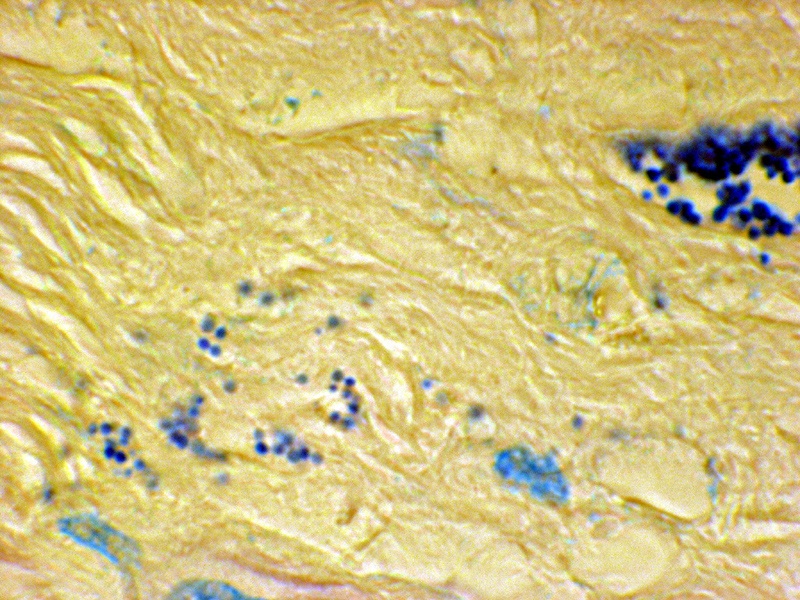

Figure 3. Tissue section from breast cancer showing a clump of non-acid-fast, blue-stained coccoid forms. Fite (acid-fast) stain, x1000, in oil.

Figure 12. Tissue section from prostate cancer. A clump of coccoid forms on the right; and extracellular forms in the stroma on the left. Fite stain, x 1250, in oil.